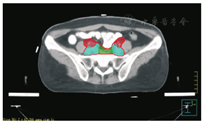

笔者所在科室对于FIGO临床分期为ⅡB期宫颈癌(阴道穹窿受侵、宫旁受侵近盆壁)的调强放疗流程及靶区CTV勾画范围建议如下。对其定位前准备工作包括:患者于定位前30~40 min排空膀胱,再饮水500 mL(含造影剂碘化醇10 mL),显影小肠。对其靶区CTV勾画具体操作步骤为:让患者取仰卧位,身下垫胸、腹平板,双手抱肘并上抬置于额头,热塑体膜固定(上腹至大腿上约1/3处);待热塑体膜冷却成形后,激光灯下于体前正中和两侧分别置铅点(尽可能靠近靶区中心)。此时尽可能行CT增强扫描,以更清楚显示解剖位置;对造影剂过敏、高龄、伴有严重并发症等不适合行CT增强扫描者,仅进行平扫。CT检查的扫描范围为:第一腰椎体上缘至坐骨结节下2 cm,层厚为5 mm,若腹主动脉旁淋巴结转移,则上移至隔顶;若全阴道浸润、腹股沟淋巴结转移,则下移至外阴下4 cm。其中,对靶区CTV勾画:放疗前,应常规实施CT、MRI或PET-CT检查,以明确肿瘤靶区范围及是否存在远处转移(部分远处转移病变,可与原发部位同时进行放疗)。对于其GTV勾画,则包括临床肉眼可见或可触及的,或可通过检查手段证实的肿瘤区域,具体包括宫颈肿瘤、受侵宫旁及阴道组织。MRI检查是确定软组织及宫旁受侵的较理想方法。若腹膜后淋巴结转移,需对淋巴结照射剂量进行加量时,CTV则应单独勾画转移淋巴结靶区。CTV勾画分为局部肿瘤区域和淋巴引流区域。局部肿瘤区域CTV勾画,包括局部肿瘤GTV及显微镜下可见的亚临床肿瘤病变,首先为宫颈、宫体、宫旁和阴道CTV勾画。①宫颈CTV:勾画全部宫颈。②宫体CTV:勾画全部宫体。③宫旁CTV:勾画上界为乙状结肠跨过子宫及输卵管处,下界为泌尿生殖膈,前界为膀胱后壁/髂外血管后缘。若子宫前倾明显,则子宫前界为宫旁前界,后界为宫骶韧带和直肠系膜前缘,内侧界为子宫颈阴道,外测界为骨盆壁,不包括肌肉和骨。值得注意的是:若宫骶韧带受累,CTV勾画则需将整个宫骶韧带全部包括在内,此时直肠系膜淋巴结及直肠周淋巴结均应包括在内。对于FIGO临床分期为ⅢB期及以上者,CTV应将直肠周淋巴结勾画在内,宫旁靶区与髂淋巴结及闭孔淋巴结区重叠。④阴道CTV:若阴道无受侵,则勾画阴道上段1/2,若上段受侵,则勾画阴道上段2/3,若阴道广泛浸润,则勾画全阴道。其次,盆腔淋巴结引流区包括宫颈旁、宫旁、闭孔、髂内、髂外、骶前及髂总淋巴结CTV勾画,依照其血管走行进行勾画。①髂总动脉CTV:上界为腹主动脉分叉下缘,下界为髂总动脉分叉下缘;前界为血管前7 mm,后界为血管后7 mm;内侧界为血管内侧7 mm,外侧界为血管外7 mm,腰大肌内侧缘,包括腰大肌与椎体旁间隙。②髂外动脉CTV:上界为髂总动脉分叉下缘,下界为股骨头上缘即股动脉;前界为血管前7 mm,后界为血管后7 mm;内侧界为血管内侧7 mm,以子宫、卵巢、肠管、输尿管及膀胱为界,外侧界为血管外7 mm,腰大肌及髂腰肌内侧缘。③髂内动脉CTV:紧邻髂内血管及其分支,上界为髂总动脉分叉下缘,下界为尾骨肌上缘、坐骨棘或子宫动静脉上端;前界为血管外7 mm,后界为上部以骶骨翼为准,中下部至梨状肌前缘或臀下动静脉;内侧界为血管外7 mm,外侧界为头侧髂腰肌、髂肌或骶髂关节外侧,中间为髂骨、髂腰肌或髂肌内侧缘;尾侧界为闭孔内肌或梨状肌内侧。④闭孔淋巴结CTV:上界为骶髂关节下缘连接至髂内淋巴结,下界为闭孔上缘;前界为上中部分连接到髂外,下部至耻骨后缘,后界上中部连接到髂内,下部至闭孔内肌后缘;内侧界至膀胱、子宫及肠管,沿骨盆壁向内扩18 mm,外侧界至闭孔内肌、髂肌、髂腰肌或髂骨。⑤骶前淋巴结CTV:上界为髂总分勾画范围,见图1,图2,图3,图4,图5,图6。